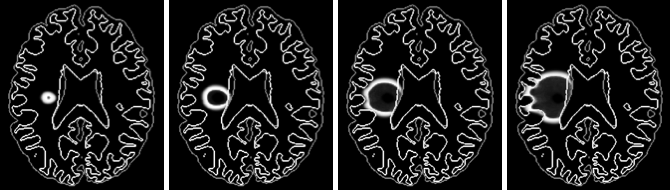

Gliome - influence des cellules invasives